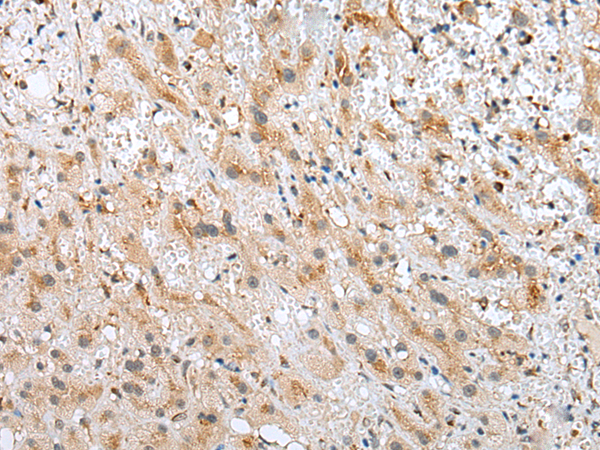

分类: 科研抗体货号: P09112别名: CFM2; FAM101A应用: IHC反应种属: Human